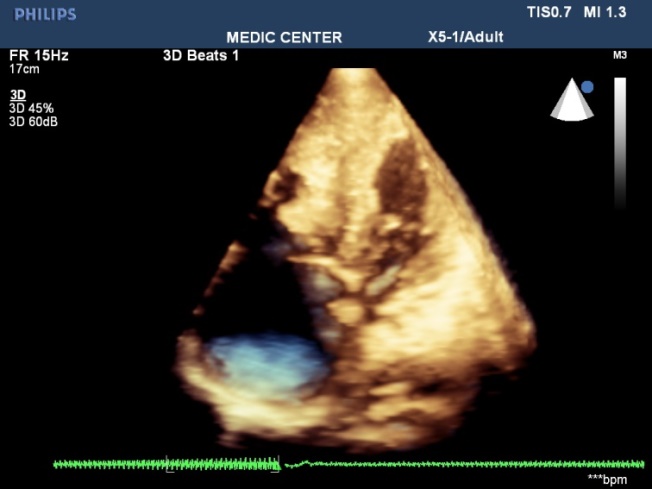

The X-plan mode can be used to estimate the maximal diameter of defect in two orthogonal planes. Three-dimensional (3D) TEE imaging is an important adjunct to 2D imaging because multiplanar reconstruction ensures that the defect is measured accurately.

Three-dimensional (3D) TEE images can be rotated to demonstrate the defect from the RA or LA side in evaluating the secundum atrial septal defect rims. This improves understanding of their shape and relationships to surrounding intracardiac structures.

Figure 26. L-R shunting secundum ASD demonstrated with color flow imaging

Figure 27. I crop mode showing simultaneously 3D and 2D images

Figure 28. Multibeats live mode without color flow imaging visualizes a secundum ASD

Figure 29. Multibeats live mode with color fow mapping visualizes the L-R shunt